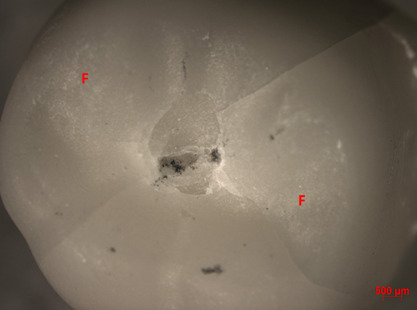

To evaluate the fracture load of bilayer ceramic crowns manufactured by Rapid Layer Technology (RLT) after different cementation protocols of the veneering ceramic to the zirconia infrastructures. Sixty epoxy resin preparations simulating a molar tooth were obtained and 60 zirconia infrastructures and feldspathic crowns were manufactured by RLT and divided into 6 groups according to the cementation protocol at the interface to veneering ceramic (n=10): Ctr- control: conventional resin cement; Al- Al2O3 sandblasting 50µm + conventional resin cement; Al/MDP- Al2O3 sandblasting (50µm) + resin cement with MDP; Sil- silicatization 30µm + conventional resin cement; Gl/HF- glaze + hydrofluoridric acid (5%,60s) + silane + conventional resin cement; Gl- glazing as bonding agent. The feldspathic ceramic internal surface was etched with fluoridric acid (5%) + silane followed by cementation according to respective protocols. All samples were mechanically cycled (200N and 4.5x105 Pa, 37°C, 2x106 cycles, 3.4Hz) and submitted to axial compressing fracture load test (10kN, 0.5mm/min). The results(N) were submitted to descriptive and analytical statistical analysis with 1-way ANOVA, Weibull, and the Tukey test (α=0.05). ANOVA revealed that there was a significant difference among the tested groups (p<0.0001). The group Al/MDP presented the higher resistance to fracture (1972.46A N), followed by the Ctr group (1584.41B N). The characteristic strength(σ0) was significantly different (p=0.000). The crack and chipping were the predominant failures. The air-abrasion at the external surface of zirconia with Al2O3 followed by cementation with MDP resin cement, should be selected to Rapid Layer Technique when felspathic ceramic is used as veneer ceramic.

Abstract Image